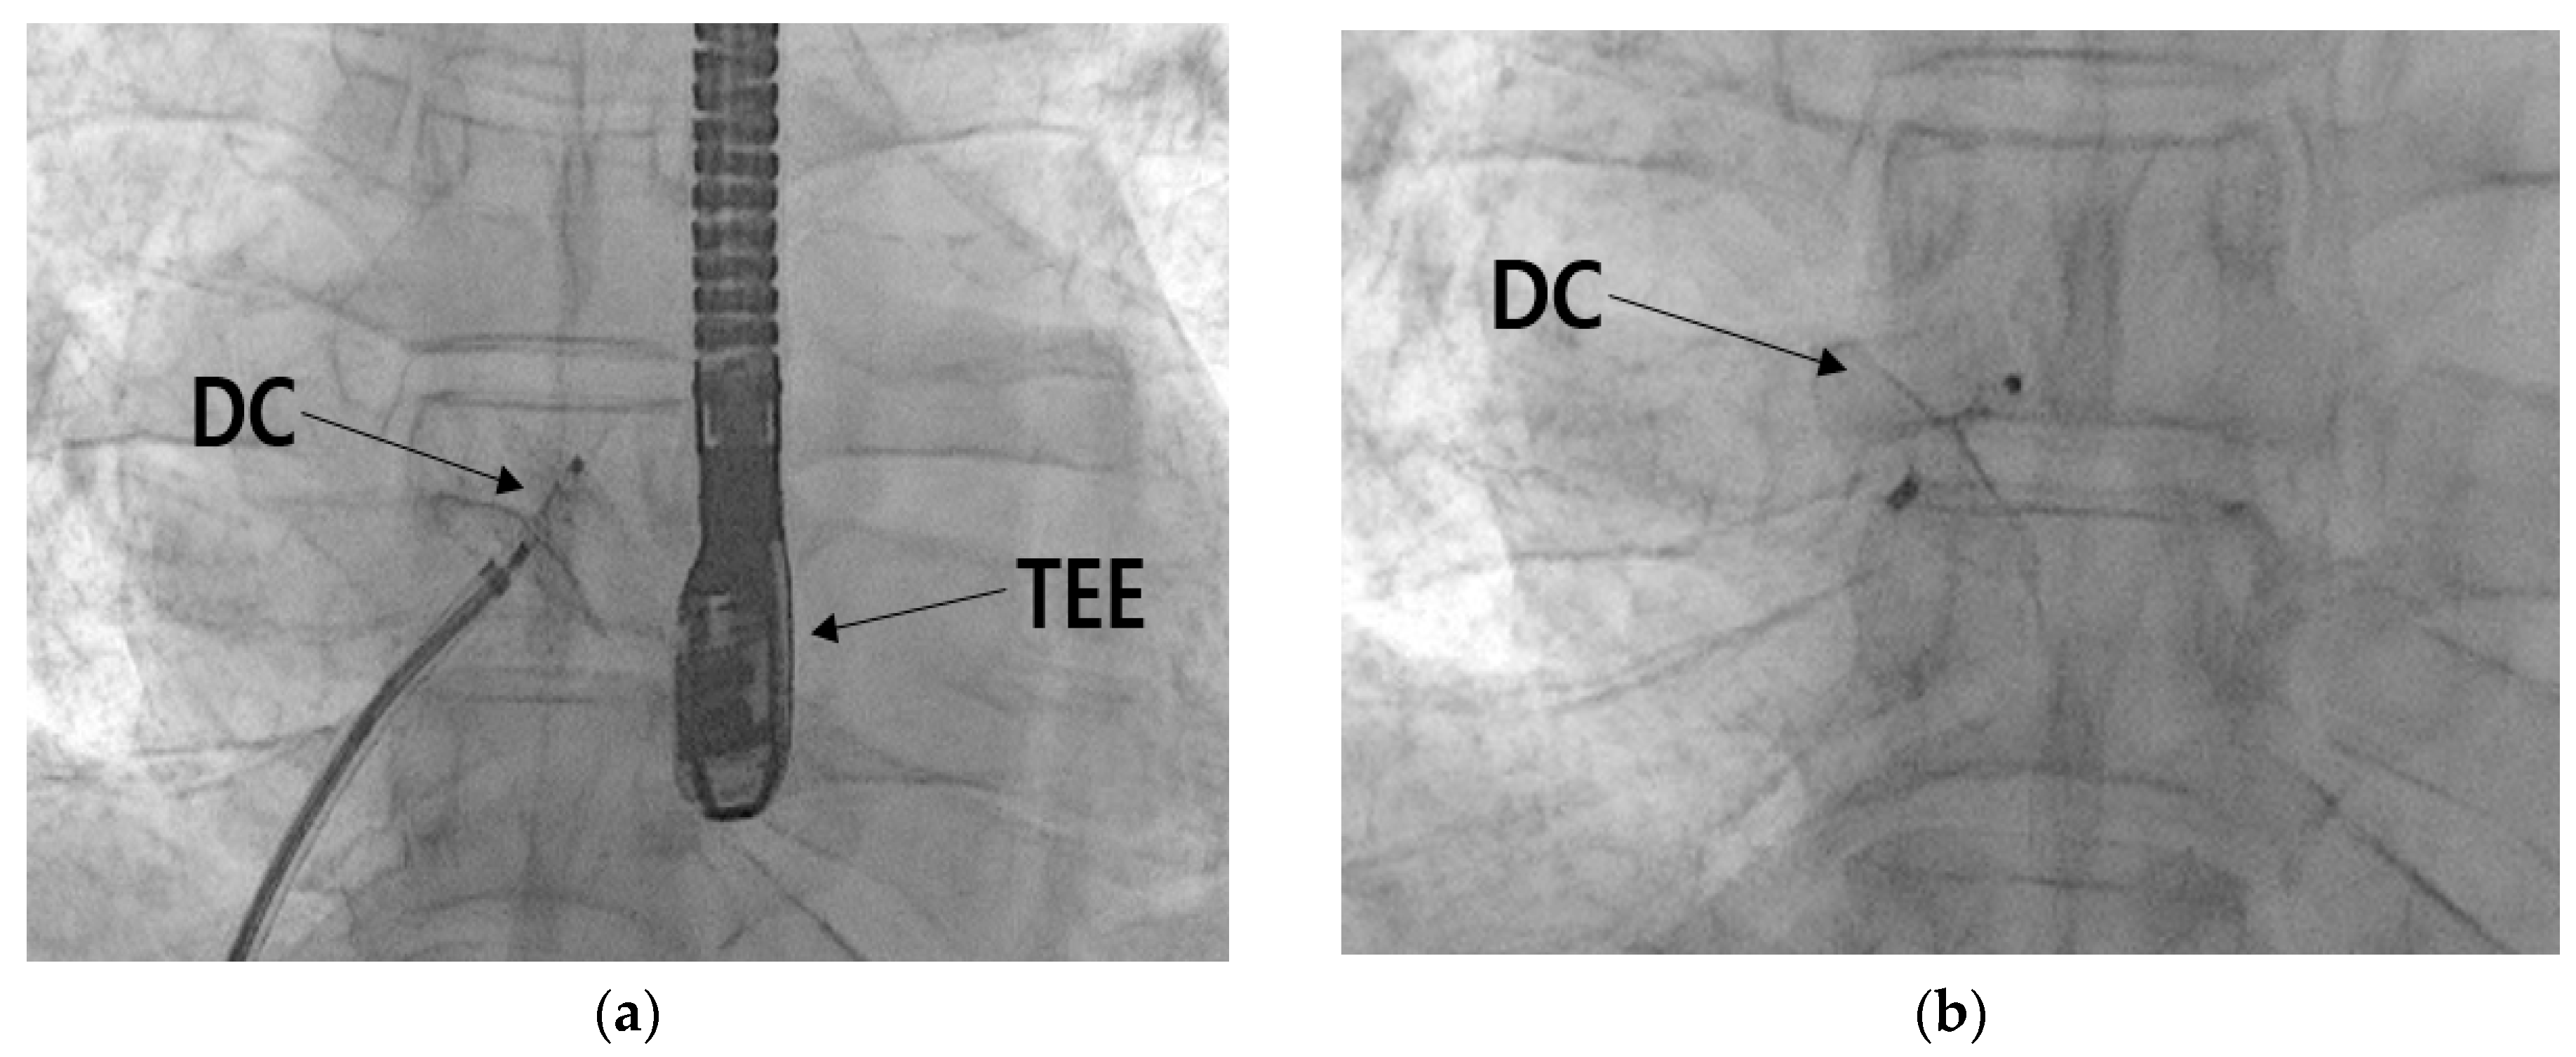

The PFO closure procedure was performed by a cardiologist. A five-French femoral sheath was introduced through the right femoral vein and subsequently replaced with a guide system (Amplatzer Trevisio 45 Delivery System, Amplater, USA) designed to facilitate the transportation of the closure device to the heart. The selected closure device was an Amplatzer PFO occluder, which measured 25 mm. Utilizing TEE in conjunction with the guidance system, the device was accurately positioned at the heart's PFO (Figure 9(a)). The closure of the PFO was then accomplished (Figure 9(b)). Following the confirmation of successful closure, the device was detached, marking the completion of the procedure. After the procedural steps, echocardiography, plain chest imaging was performed to confirm the accurate positioning and alignment of the closure device, as well as to identify any abnormalities in the surrounding structures. The procedure concluded without any observed irregularities.

Figure 9. Process of intervention to close the PFO. (a) position of the PFO device closure (DC) while guided by the transesophageal echocardiography (TEE), and (b) the PFO device closure removed from the guide system.